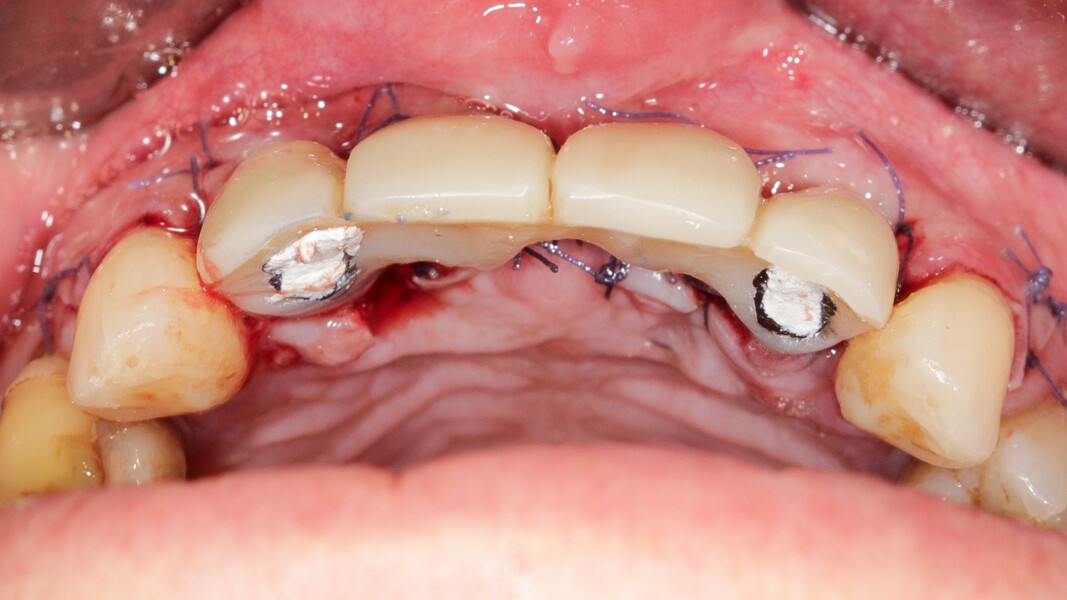

Nous réalisons un lambeau avec une incision crestale décalée en palatin en 11 et 21, sulculaire en 12, 13, 22, 23, en prenant soin de préserver les papilles interdentaires, ainsi que deux décharges verticales en distal des canines. Nous réalisons un décollement de pleine épaisseur (Figs. 28 et 29). Les dents (12, 22 et 18) sont facilement extraites et les alvéoles curetées avec soins. Deux implants (4*13) sont positionnés dans la paroi palatine des alvéoles, il subsiste une déhiscence vestibulaire en 22. Les racines de 12, 22 et 18 sont séparées dans le sens de la longueur. Les racines préparées comme indiqué ci-dessus, sont vissées en vestibulaire et en occlusal de la crête, au moyen de vis d’ostéosynthèse (diamètre 0,9 mm), afin de reconstruire la crête osseuse au niveau des inters de bridge ainsi que la paroi vestibulaire de la crête au niveau de 22 (Figs. 30 et 31). Le gap vestibulaire entre les implants et la crête ainsi que l’espace entre la crête et le greffon au niveau de 21, sont comblés avec un matériau d’origine synthétique (Collapat II Symatese). Le lambeau est tracté, suturé coronairement avec un fil tressé synthétique 5.0 (Fig. 32). Des piliers coniques droits pour prothèse plurale transvissée sont posés, et une empreinte prise à la fin de l’intervention (Fig. 33). Un provisoire est réalisé dans la journée par notre laboratoire de prothèse et posé le soir même. (Figs. 34 et 35)